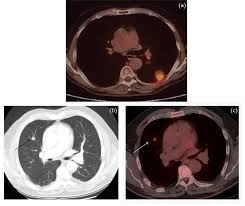

Metastatic Colorectal Cancer Symptoms Diagnosis Treatment More from i0.wp.com And sometimes, a metastasis may be found before the original (primary) tumor is found. Metastasis is the spread of cancer cells to new areas of the body, often by way of the lymph system or bloodstream. So, if colon cancer spreads to the lungs it is still called colon cancer, they just add on the name metastatic, and it becomes metastatic colon cancer. the different areas where colon cancer can spread are: In metastasis, cancer cells break away from where they first formed (primary cancer), travel through the blood or lymph system, and form new tumors (metastatic tumors) in other parts of the body. Metastatic disease (also known as stage 4) is usually not curable by todays treatments. Peritoneal metastasis from colorectal cancer origin has been associated with poor prognosis as well as poor quality of life for the patients in this terminal stage of the disease 3, 4. Management of metastatic colon cancer is usually done by a team of medical practitioners. Sometimes the metastatic tumors have already begun to grow when the cancer is first found.

Most cancer researchers have assumed that the spread, or metastasis, of tumors typically occurs later in the disease process.the general idea has been that as tumors grow and. Colorectal cancer that spreads to the lung, also called lung metastasis, is treated differently than cancer that originates in the lung. Metastatic disease (also known as stage 4) is usually not curable by todays treatments. Metastatic colorectal cancer is cancer that has metastasized. In the united states, 140,000 new cases of colon cancer are diagnosed each year, making it one of the most frequently encountered cancers. There are four stages of melanoma and these stagecoaches express the progression of the disease and which type of medication would be needed. Cancer has spread to more than one area or organ that is not near the colon and/or rectum, such as the liver, lung, or a distant lymph node. Although use of chemotherapy may improve survival and may rare. In fact, metastasis can start extremely early on, when the original colon tumor is smaller than the tip of a pencil, the nci says. Patients diagnosed with stage iv colon cancer have an increasing number of treatment options as. Despite having an advancing condition, the timing of death is very unpredictable. Has anyone ever had metastatic, terminal colon cancer with liver metastasis and bowel perforation? Metastatic colorectal cancer is different from recurrent colorectal cancer.

Colorectal cancer that spreads to the lung, also called lung metastasis, is treated differently than cancer that originates in the lung. There is no sign that the cancer has spread outside of the colon or rectum. 5  however, a 2017 study found survival rates for those with stage 4 colon cancer that metastasized to the liver and were candidates for removal of the liver metastases at the same time as colon surgery improved to up to 70% 6 . This is also referred to as advanced colon cancer or stage iv colon cancer. Another name for it is metastatic, or stage iv, colon cancer. A metastatic cancer, or metastatic tumor, is one that has spread from the primary site of origin, or where it started, into different areas of the body. This may include the liver, lungs, bones, distant lymph nodes or other sites. And sometimes, a metastasis may be found before the original (primary) tumor is found. Metastatic colorectal cancer is cancer that has metastasized. Patients diagnosed with stage iv colon cancer have an increasing number of treatment options as. Peritoneal metastasis from colorectal cancer origin has been associated with poor prognosis as well as poor quality of life for the patients in this terminal stage of the disease 3, 4. About 20% to 25% of people are first diagnosed with colon cancer. Cancer has spread to one area or organ that is not near the colon and/or rectum, such as the liver, lung, or a distant lymph node.